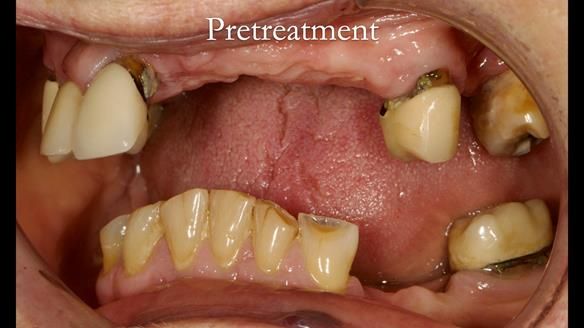

Aesthetically and functionally poor RPDs were replaced for Eileen, a 74 year old woman.

Referred to me by her general dental practitioner specifically for replacement RPDs.

Dental concerns

“Top denture loose making conversation difficult at times. Also, appearance isn’t good. Teeth uneven”

Diagnoses

- Missing teeth in the upper and lower jaws

- Upper and lower metal based RPDs, poorly fitting, worn occlusal surface, reverse curve aesthetics, lacking support

- Poor dental appearance with reverse incisal curve

- The upper right central and lateral incisors with post crowns. Healthy and functionally secure but with poor appearance, contributing to the reverse curve.

- Moderate to heavily restored dentition with deep overbite (Class 2 div II)

- Yellowish lower front teeth with small amount of wear.

- The lower right canine (LR3) is worn with MOD cavity.